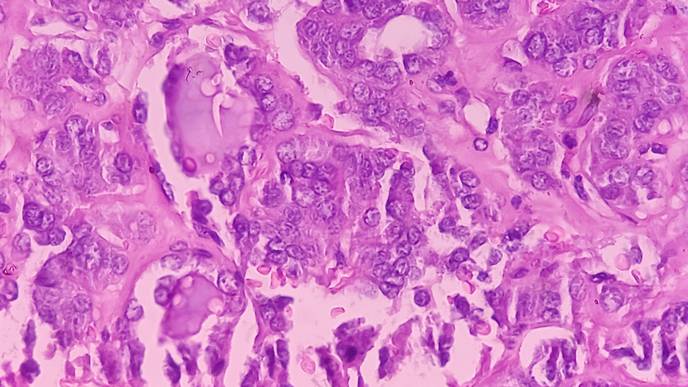

Axi-cel CAR T targets the CD19 molecule on large B-cell lymphoma cells. The ZUMA-7 trial demonstrated that axi-cel reduced the risk of disease progression, the need for new therapy, or death by 60% compared to standard therapy. Despite these positive outcomes in event-free survival and overall survival, some patients did not respond well to therapy or relapsed quickly after treatment.

A team of researchers led by Dr. Frederick L. Locke, chair of the Blood and Marrow Transplant and Cellular Immunotherapy Department at Moffitt Cancer Center, analyzed tumor gene expression patterns from patient samples and determined that a B-cell gene expression signature and CD19 protein expression were significantly associated with improved event-free survival for patients treated with axi-cel but not standard therapy. Patients with lower tumor cell levels of CD19 had gene expression patterns associated with immune suppression. These observations suggest that the tumor immune environment may play an important role in regulating axi-cel therapy and outcomes. In addition, biomarkers associated with improved outcomes to axi-cel therapy decreased as patients had more treatments, suggesting that receipt of axi-cel in earlier lines of treatment is essential to ensure better patient outcomes.